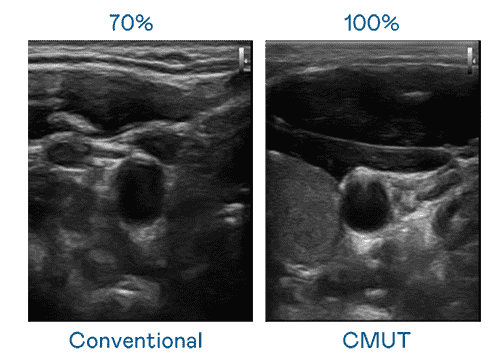

CMUT 技术是一种用电容式微机电元件来产生超音波讯号的技术。。。与传统 PZT 压电式技术相比,,,CMUT 频宽增加 30%,,,,更宽频的超音波讯号让影像解析度大幅提升,,是实现高影像品质医疗超音波扫描、、、促进精准医疗发展的关键技术。。

大频宽带来超清晰影像

超音波影像的解析度高低,,,首先取决于探头能发出的讯号频宽。。。Wepay CMUT 可提供高清晰的超音波讯号,,提供高频宽、、高灵敏度、、、、影像纹理细节更高的超音波影像,,,,协助医护人员缩短影像判读时间及利用精准的医疗影像进行诊断。。。